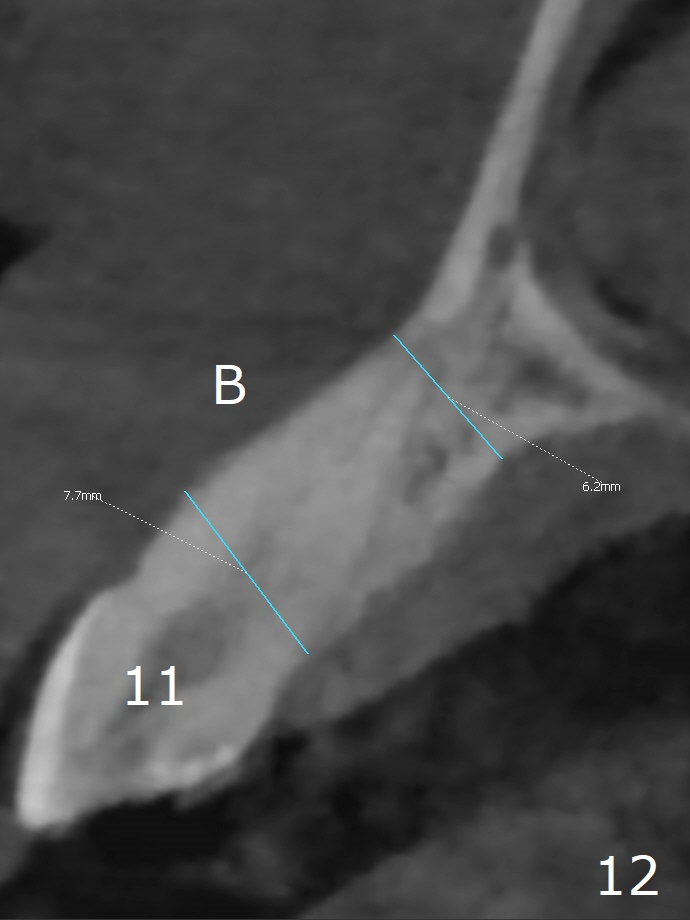

When the tooth #6 with loose crown and post (Fig.1) is extracted, there is no granulation tissue in the socket with the thin intact buccal plate. As planned, osteotomy is initiated in the mesio-palatal slope of the socket (Fig.2 red dashed line). After osteotomy for 3x20 mm (gingival level), a 3.8x15 mm dummy implant is placed partially (Fig.3 D). A final implant with the same dimension is placed with > 50 Ncm (Fig.4). Before and after placement of a 4.5x5(3) mm abutment, Vera graft is placed in the remaining socket space (mainly buccal, Fig.5 *). As routine, an immediate provisional is fabricated with occlusal clearance. The gingiva looks healthy around the provisional 1 week postop (Fig.6 P). Adjust and polish the mesioocclusal composite at #5 if necessary before impression. The bone graft appears to remain in place 4.5 months postop (Fig.7). A bevel buccal subgingival margin is placed prior to impression. The bone density around the coronal portion of the implant increases 9 months postop (4 months post cementation, Fig.8). There is no gingival erythema or edema around the implant crown at #6 ten months post cementation (Fig.6, as compared to preop condition and that of the neighboring crown (*)). Both the buccal and palatal plates are thin or absent 1 year 5 months post cementation (Fig.10,11, as compared to Fig.12 for the tooth #11 (thin buccal bone)). Socket shield should be done with a smaller implant.